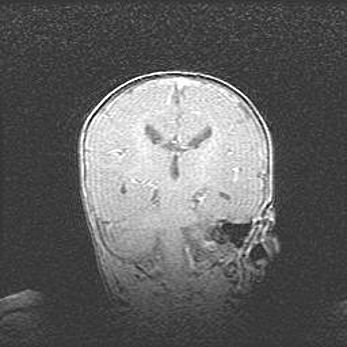

Наружная гидроцефалия с возможной атрофией височных областей.

Возраст: 28 дней

Вес: 3670 г

Пол: мужской

Окружность головы: 38 см

Срок гестации: 40 недель

Гидроцефалия головного мозга у новорожденных – это заболевание, которое характеризуется скоплением избыточного количества спинномозговой жидкости в желудочковой системе головного мозга в результате затруднения её перемещения от места выработки к месту поглощения в кровеносную систему или вследствие нарушения абсорбции. При открытой наружной форме гидроцефалии у новорожденных расширяются и переполняются субарахноидные пространства.

При нормотензивных  формах,  которые,  как  правило,  являются  следствием  перенесенных ишемических  повреждений  паренхимы  мозга,  возможно  сочетание микроцефалии  с нормотензивной гидроцефалией. В основе данных изменений лежит атрофия больших полушарий с преимущественной  локализацией  в  лобно-височных  областях.